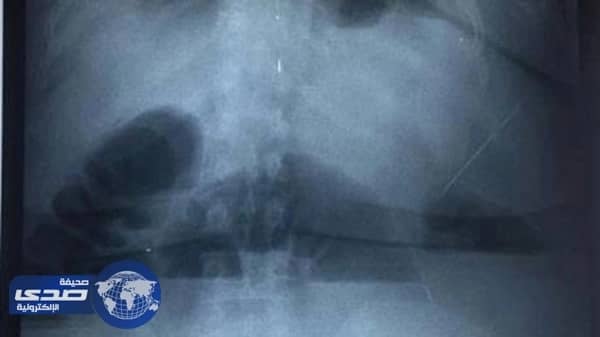

أقدمت عراقية أم لخمسة ابناء ، على تناول المناديل الورقية للتخلص من الوزن الزائد والكرش ما اسفر عن اصابتها بآلآم شديدة بالبطن .

وكان قد أعلن مدير مستشفى طوارئ شرق أربيل ، بلين كويي أن مريضة نقلت إلى المستشفى بعد إصابتها بآلام في البطن بسبب تناولها ” مناديل ورقية “، مضيفاً أنها تتلقى الآن الرعاية الصحية.

وقال كويي إن “المريضة وهي أم لخمسة أبناء، نقلت الأربعاء، إلى المستشفى، وأخبرت الأطباء بأنها تناولت المناديل الورقية، لخفض وزنها”، متابعاً أننا “نعمل على تقديم العلاج اللازم لها”.

من جانبه، قال مسؤول إعلام المستشفى، كرمانج محمد إن “المريضة أكدت أنها كانت تتناول بين 20 إلى 25 منديلاً ورقياً يومياً لخفض الوزن منذ الـ 10 مارس2017، وأنها أصيبت بألم حاد في بطنها منذ مساء الثلاثاء، ومن المحتمل أن يتطلب علاجها إجراء عملية جراحية لها”.